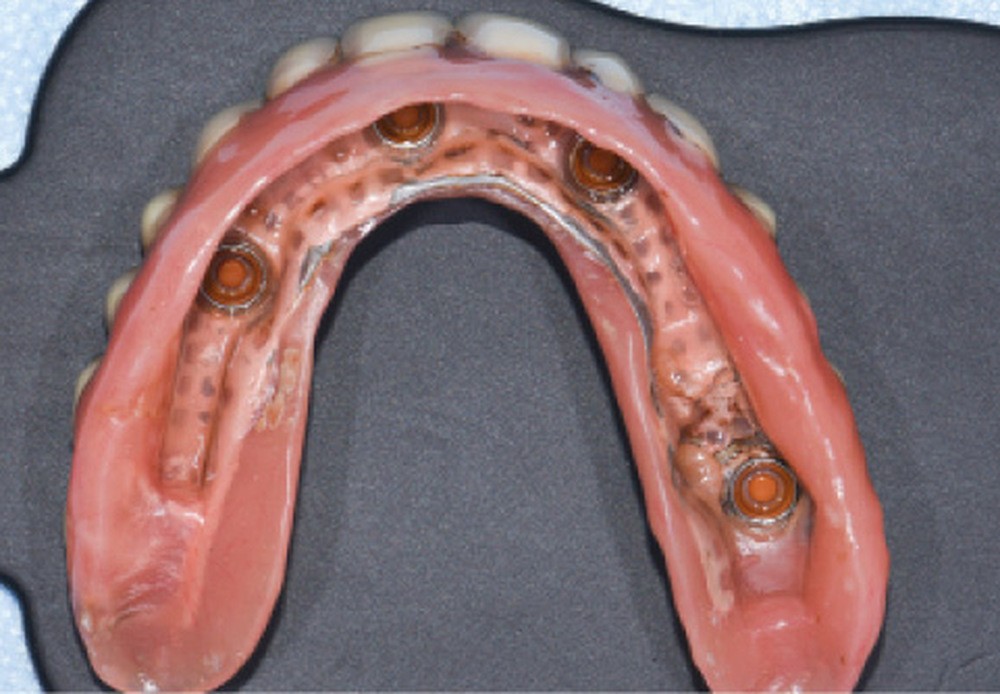

Une réhabilitation par PACSI maxillaire a été réalisée dix ans auparavant sur 5 implants en place de 13, 12, 21 et sur 24 et 26 (fig. 2a et b). Dans le cadre du plan de traitement initial, 6 implants avaient été indiqués. L’un d’entre eux, en position distale dans le secteur I, n’a jamais été ostéointégré. La patiente ne souhaitant plus de chirurgie, il avait donc été décidé de réaliser une prothèse sur 5 implants. La barre est directement connectée aux implants. À la mandibule, la patiente présente également une PACSI sur 2 implants associés à 2 piliers Locator®.

Lors de l’examen clinique, après dépose de la prothèse et dévissage de la barre, le constat est alarmant : présence de plaque abondante…